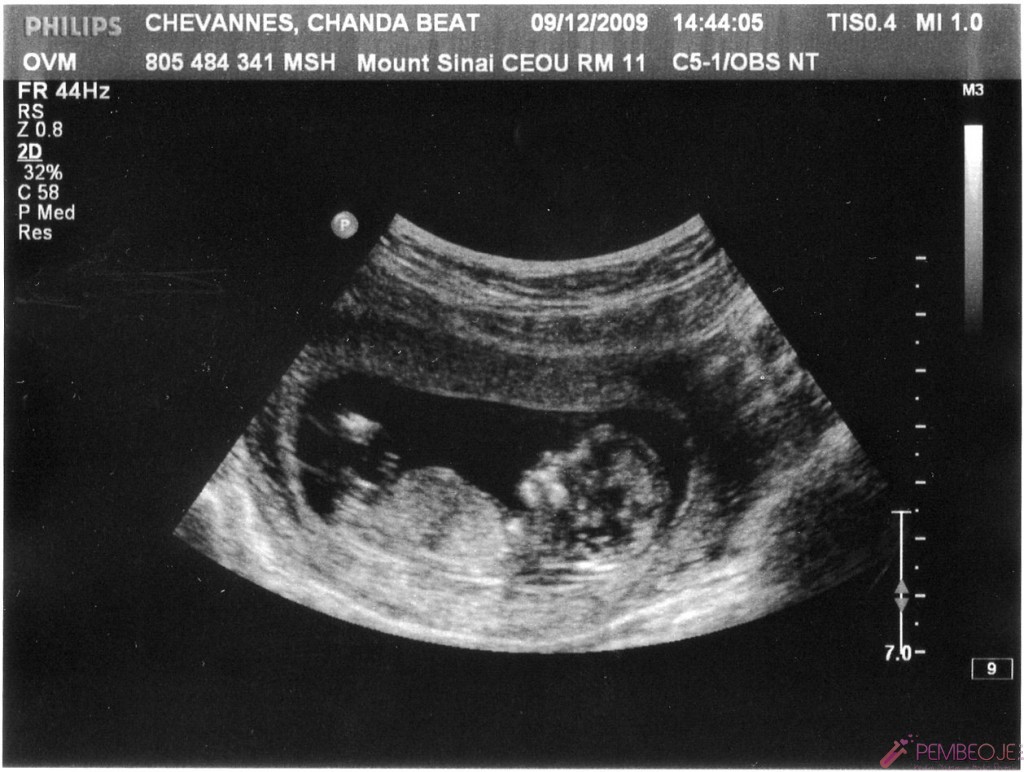

Vajinal ultrason görüntülemeleri, karın bölgesinden yapılan görüntülemelere göre daha erken sonuç verecektir.

Bebek kesesi de bu dönemde çiftler tarafından görülür. Anne ve baba adayları hamilelik de ultrasonda bebek ne zaman görülür sorunusun sık sık sormaktadırlar. Haftalarında ise ultrason ile gebelik kesesinin görüldüğü belirtilir. Bebeğin sağda olması erkek, solda veya sola yakın olması kız olduğunu gösterir. Gebelik öğrenildiği ilk günden son güne kadar süren eşsiz bir serüven. Gebe kadında ultrason muayenesi vajinadan ve karından olmak üzere iki şekilde yapılabilir. Hamilelik sürecinin en heyecan verici olayı hem anne hem de baba için bebeğin kalp atışlarının ilk kez dinlendiği andır. Gebelik döneminde bebeğin kalp atışları farklı haftalarda izlenebilir. Hamileliğin başlama zamanın ilk ne zaman olduğunun bilinmesi yani en son regl kanamasının ilk tarihi bilinmesi gerekir.

Haftalarda yapılacak vajinal ultrasonda bebeğin konumu belirlenerek bunun üzerinden cinsiyet tahmininde bulunulmaktadır. Anne ve baba adayları hamilelik de ultrasonda bebek ne zaman görülür sorunusun sık sık sormaktadırlar. Için yorumlar kapalı 785 kez görüntülendi anne adayları hamile kaldıklarını öğrendikten sonra bebeklerini görmek kalp atışlarını duymak için farklı bir heyecana bürünürler. Hamileyim ama bebeğimin kesesi görünmedi, bu bebeğin kesesi kaçıncı haftada oluşuyor neden göremiyorum. Ultrasonda gebelik kesesi ancak gebeliğin 5. Ultrasonda gebeli̇k kesesi̇ ne zaman görülür?

Anne adayları bebeklerini daha doğmadan önce görmek isterler. Ultrasonda bebek kaçıncı haftada görülür? Ultrasonda muayene işlemi bebek kesesi görülmesi ve bebeğin sonraki aşamalarının izlenmesi adına karından ya. Anne adayları hamile kaldıklarını öğrendikten sonra bebeklerini görmek kalp atışlarını duymak için farklı bir heyecana bürünürler. Ultrason muayenesi karından ve vaginadan olmak üzere iki farklı şekilde yapılır. Embriyo transferinden sonra gebelik oluşumu için 12 gün beklenmelidir.

Hamileliğin başlama zamanın ilk ne zaman olduğunun bilinmesi yani en son regl kanamasının ilk tarihi bilinmesi gerekir. Sevgili melekler, anne olmak isteyen bayanları en merak ettiği konuların başında gebe kalındığında bebeğin ne zaman ultrasonda görülebileceği gelir. Haftasında vaginal ultrasonda gebelik kesesinin görülmesi mümkündür. Gebelik döneminde bebeğin kalp atışları farklı haftalarda izlenebilir. Haftaya kadar düşük riski yüksektir. Vajinal ultrasonda gebelik kesesi ne zaman görülür?

Bu konu bebek ultrasonda görülme zamanı hakkında bilgiler vermektedir. Ultrason muayenesi karından ve vaginadan olmak üzere iki farklı şekilde yapılır. İlk ultrason muayenesi ne zaman yapılmalı? Vajinal ultrasonda gebelik kesesi ne zaman görülür sorusunun yanıtı hamileliğin 5. Gebelik kesesi ultrasonda ne zaman görülür ? Haftasında vaginal ultrasonda gebelik kesesinin görülmesi mümkündür.

Anne adaylarının hamilelik belirtileri ortaya çıktıktan sonra ve hamile olduğunu öğrendikten sonra kesede bebek ne zaman görülür veya hamilelikte kese ne zaman görülür soruları sorulmaya başlamaktadır. Gebe kadında ultrason muayenesi vajinadan ve karından olmak üzere iki şekilde yapılabilir. Ultrasonda muayene işlemi bebek kesesi görülmesi ve bebeğin sonraki aşamalarının izlenmesi adına karından ya.

Anne adaylarının büyük bir heyecanla beklediği ultrason döneminde neler görülür, bebeğin ilk kalp atışı ne zaman dinlenir ve bebeğin hareketleri ilk ne zaman görülür hepsini sizler için hazırladık. Bebeğin kalp atışları ne zaman duyuluyor. Ultrasonda gebelik kesesi ancak gebeliğin 5.

İlk ultrason muayenesi ne zaman yapılmalı? Ultrasonda bebek ne zaman, hangi hafta görülür? Anne adaylarının hamilelik belirtileri ortaya çıktıktan sonra ve hamile olduğunu öğrendikten sonra kesede bebek ne zaman görülür veya hamilelikte kese ne zaman görülür soruları sorulmaya başlamaktadır.

Haftasında vaginal ultrasonda gebelik kesesinin görülmesi mümkündür. Ultrasonda bebeğin ne zaman görüleceği, cinsiyeti, kalp atışları bu sorulardan sadece birkaçı… Bebeğin ultrasondaki ilk görüntüsü, gebeliğin 4,5 veya 5.

Vajinal ultrasonda gebelik kesesi ne zaman görülür? Gebelik kesesi bebeğe dair görülen ilk oluşumdur. Haftasında vaginal ultrasonda gebelik kesesinin görülmesi mümkündür.

Haftasında vaginal ultrasonda gebelik kesesinin görülmesi mümkündür. Vajinal ultrason görüntülemeleri, karın bölgesinden yapılan görüntülemelere göre daha erken sonuç verecektir. Ultrason muayenesi karından ve vaginadan olmak üzere iki farklı şekilde yapılır.

Anne adaylarının büyük bir heyecanla beklediği ultrason döneminde neler görülür, bebeğin ilk kalp atışı ne zaman dinlenir ve bebeğin hareketleri ilk ne zaman görülür hepsini sizler için hazırladık. Bu risk vajinal ultrason yapılsa da, yapılmasa da aynıdır. Vajinal ultrasonda gebelik kesesi ne zaman görülür sorusunun yanıtı hamileliğin 5.

Anne adaylarının büyük bir heyecanla beklediği ultrason döneminde neler görülür, bebeğin ilk kalp atışı ne zaman dinlenir ve bebeğin hareketleri ilk ne zaman görülür hepsini sizler için hazırladık. Ultrason muayenesi karından ve vaginadan olmak üzere iki farklı şekilde yapılır. Vajinal ultrasonda gebelik kesesi ne zaman görülür?

Haftalarında ise ultrason ile gebelik kesesinin görüldüğü belirtilir. Vajinal ultrasonda gebelik kesesi ne zaman görülür? Gebelik ultrasonda ne zaman görülür?

Ultrason muayenesi karından ve vaginadan olmak üzere iki farklı şekilde yapılır. Gebelik kesesi ultrasonda ne zaman görülür ? Ultrasonda bebek kaçıncı haftada görülür?

Gebe kadında ultrason muayenesi vajinadan ve karından olmak üzere iki şekilde yapılabilir. Ultrosonda bebek ne zaman görülür. Gebelik kesesi ne zaman görülür en çok merak edilen soruların başında gelmektedir.

Vajinal ultrasonda gebelik kesesi ne zaman görülür sorusunun yanıtı hamileliğin 5. Gebelik kesesi oluştuktan sonra içinde embriyonun görünmesi yaklaşık 1 haftalık ya da 10 günlük bir periyodu içerir. Için yorumlar kapalı 785 kez görüntülendi anne adayları hamile kaldıklarını öğrendikten sonra bebeklerini görmek kalp atışlarını duymak için farklı bir heyecana bürünürler.

Hafta içinde çiftler bebeklerini görmüş olur. Bebeğin kalp atışları ne zaman duyulur? Ultrasonda gebelik kesesi ancak gebeliğin 5.

Anne adaylarının hamilelik belirtileri ortaya çıktıktan sonra ve hamile olduğunu öğrendikten sonra kesede bebek ne zaman görülür veya hamilelikte kese ne zaman görülür soruları sorulmaya başlamaktadır. Vajinal ultrason görüntülemeleri, karın bölgesinden yapılan görüntülemelere göre daha erken sonuç verecektir. Anne adayları bebeklerini daha doğmadan önce görmek isterler.

Bebeğin ultrasondaki ilk görüntüsü, gebeliğin 4,5 veya 5. Haftaya kadar düşük riski yüksektir. Gebelik kesesi ultrasonda ne zaman görülür ?

Ultrasonda bebek kaçıncı haftada görülür? Haftalarda yapılacak vajinal ultrasonda bebeğin konumu belirlenerek bunun üzerinden cinsiyet tahmininde bulunulmaktadır. Vajinal ultrasonda gebelik kesesi ne zaman görülür?

Haftalarında vajinal ultrason ile görüntülenebilir. Tüp bebek tedavisinde ultrasonda kese ne zaman görülür? Ultrasonda bebek ne zaman, hangi hafta görülür?

Gebelik kesesi bebeğe dair görülen ilk oluşumdur. Hamileliğin başlama zamanın ilk ne zaman olduğunun bilinmesi yani en son regl kanamasının ilk tarihi bilinmesi gerekir. Ultrosonda bebek ne zaman görülür.

Gebelik döneminde bebeğin kalp atışları farklı haftalarda izlenebilir. Gebelik ultrasonda ne zaman ve hamileliğin kaçıncı haftasında görülür? Bu hafta içinde kesede embriyo bulunmuyor ise hamilelikte boş kese oluşumu yönünde teşhis koyulur.

Bebek kesesi de bu dönemde çiftler tarafından görülür. Ultrasonda bebek ne zaman, hangi hafta görülür? Bu sorunun cevabı oldukça oldukça basittir.

Hamileyim ama bebeğimin kesesi görünmedi, bu bebeğin kesesi kaçıncı haftada oluşuyor neden göremiyorum. Kese içinde bebek görmek için 7. Gebelikte kese içinde bebek ne zaman görülür.

Için yorumlar kapalı 785 kez görüntülendi anne adayları hamile kaldıklarını öğrendikten sonra bebeklerini görmek kalp atışlarını duymak için farklı bir heyecana bürünürler. Vajinal ultrasonda gebelik kesesi ne zaman görülür? Haftalarında ise ultrason ile gebelik kesesinin görüldüğü belirtilir.

Ultrasonda gebeli̇k kesesi̇ ne zaman görülür? Hafta içinde çiftler bebeklerini görmüş olur. Bebeğin ultrasondaki ilk görüntüsü, gebeliğin 4,5 veya 5.

Hamilelik sürecinin en heyecan verici olayı hem anne hem de baba için bebeğin kalp atışlarının ilk kez dinlendiği andır. Gebe kadında ultrason muayenesi vajinadan ve karından olmak üzere iki şekilde yapılabilir. Gebelik kesesi ne zaman görülür en çok merak edilen soruların başında gelmektedir.